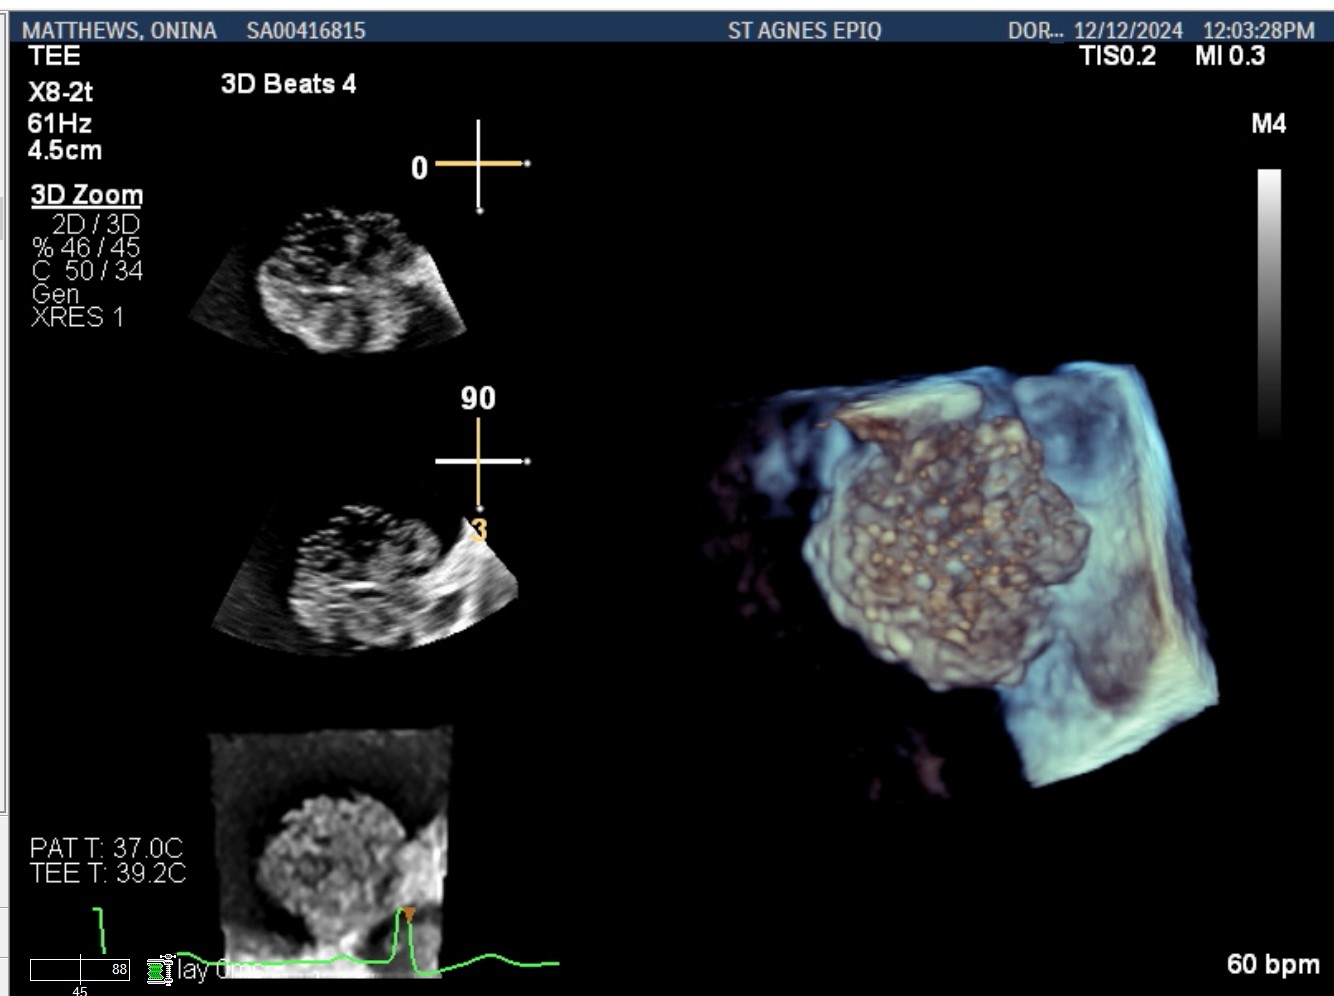

Case Presentation: A 70-year-old woman was evaluated for a TAVR workup due to recent worsening of fatigue and dyspnea. Physical examination revealed grade three ejection systolic murmur with diminished S2 and severe aortic stenosis was noted on transthoracic echocardiogram. Cardiac CT showed an atrial mass. Transesophageal echocardiography demonstrated a heterogenous left atrial mass measuring 2.7 x 2.4 cm; originates from the tip of the Coumadin ridge, independently mobile with a dandelion-like gelatinous appearance, and did not take up Definity contrast (Figures 1, 2, 3). The patient underwent surgical aortic valve replacement with mass excision through the interatrial septum. Pathologic examination revealed 2.5 x 2.2 x 1.5 cm tan-white, villous, gelatinous soft tissue consistent with fiberoelastoma.